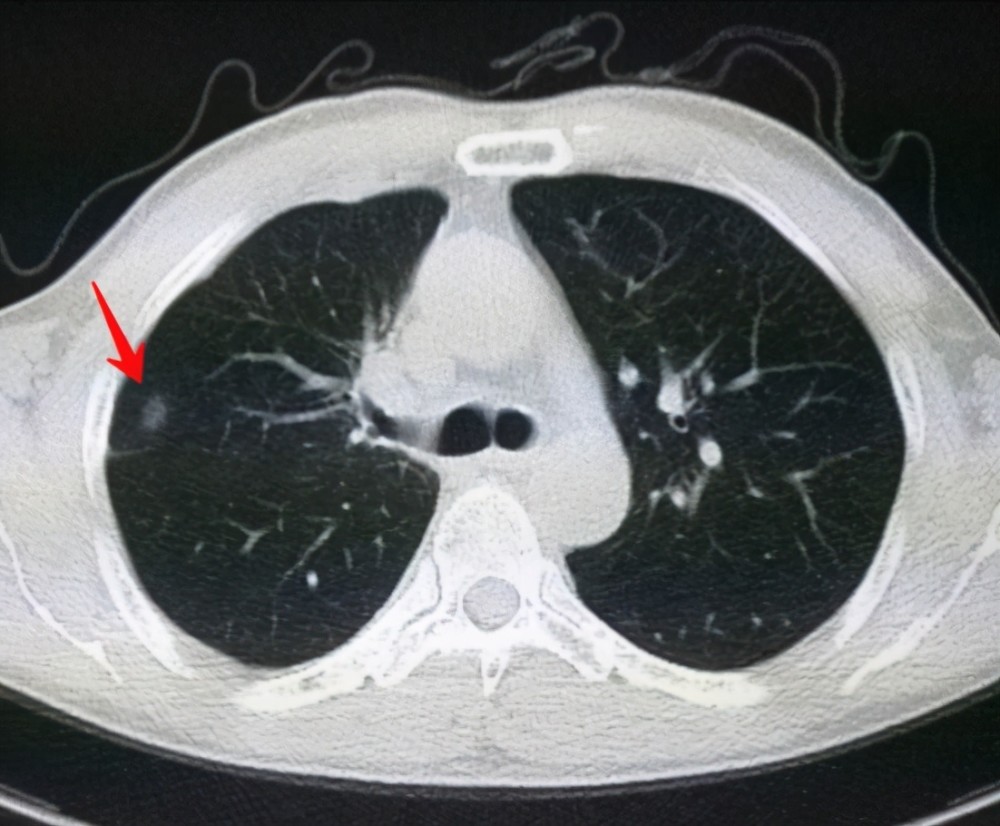

肺結(jié)節(jié)是一種常見的肺部疾病,其發(fā)病率逐年上升,雖然肺結(jié)節(jié)多數(shù)情況下是良性的,但也有可能惡化為肺癌,了解肺結(jié)節(jié)的形成原因?qū)τ陬A(yù)防和治療具有重要意義,本文將為您詳細(xì)解析肺結(jié)節(jié)的形成機(jī)制。